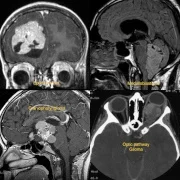

At our advanced Neurosurgery Center in Thane, we specialize in brain tumor surgery with a focus on both complete tumor removal and the preservation of neurological functions. Using modern techniques such as microsurgery, endoscopic brain surgery, and neuronavigation systems, our neurosurgeons ensure safe and precise treatment. Whether it is a glioma, meningioma, pituitary tumor, or metastatic brain tumor, we provide personalized surgical care for the best outcomes. Patients benefit from shorter hospital stays, faster recovery, and improved quality of life after surgery.

– Brain Tumors

– Pediatric Brain Tumors

– Skullbase Tumors

– Ventricular Brain Tumors